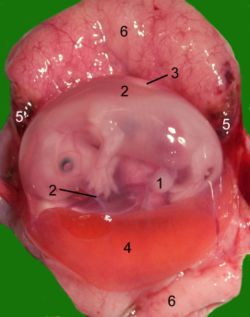

بطانة الرحم هو الغشاء المبطن لجدار الرحم الداخلي لدى إناث الثدييات.

بطانة الرحم تمنع الإلتصاقات بين الجدار الداخلي للرحم و بالتالي يظل مجوفاً. و أثناء الدورة الشهرية تنمو بطانة الرحم من حيث السُمك و كثافة الأوعية الدموية والغدد بحيث يشكل المناخ الأمثل لاستقبال زرع الجنين إذا كانت قد حدثت عملية الإخصاب.